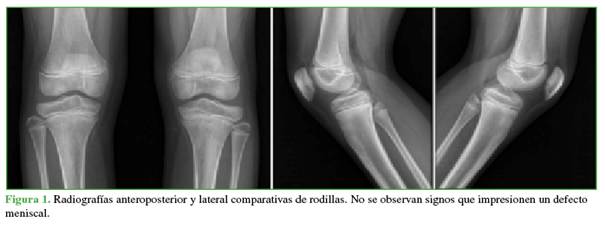

Varón de 14 años, asmático y deportista, que consultó en el Servicio de Urgencias, por gonalgia izquierda, de 2 semanas de evolución, mientras realizaba el entrenamiento de fútbol. Tenía un dolor persistente, asociado a claudicación y sensación de bloqueo intermitente. Tras la evaluación inicial y la toma de radiografías (Figura 1), se optó por el manejo ambulatorio ante la sospecha de un esguince. Los síntomas disminuyeron levemente, aunque el bloqueo articular cesó.